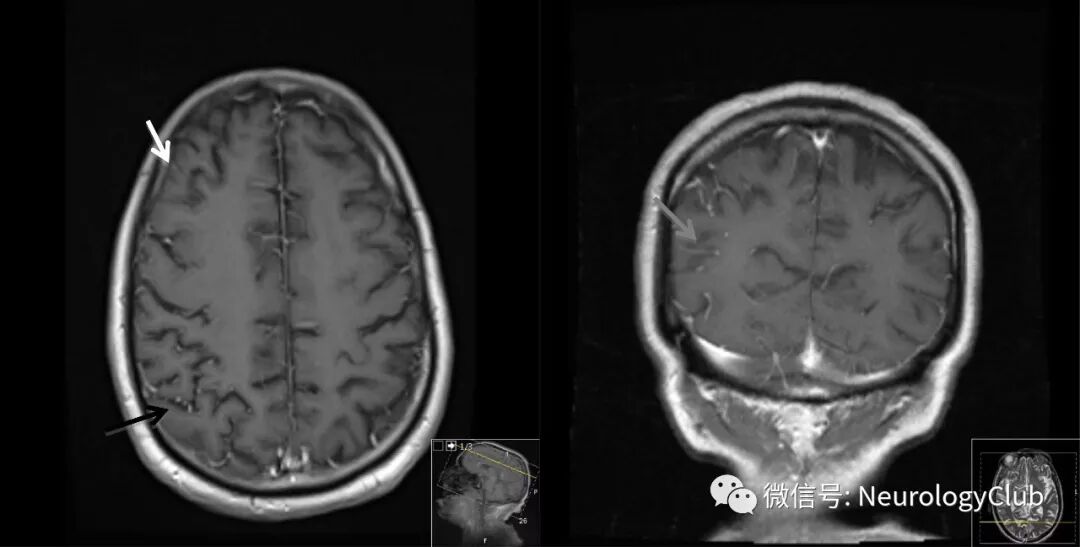

(图:头颅增强MRI可见脑实质结节样[灰箭]和软脑膜[白箭]强化,伴微脓肿形成[黑箭])

本例患者MRI可见脑实质结节样和软脑膜强化,伴微脓肿形成和脑脊液糖含量减低,以及静脉注射海洛因病史,提示可能为酵母感染。患者入急诊后便给予针对性的抗真菌治疗和经验性抗生素覆盖,临床症状迅速好转。入院12小时后,脑脊液涂片证实为白色念珠菌。后经脑脊液培养进一步证实。